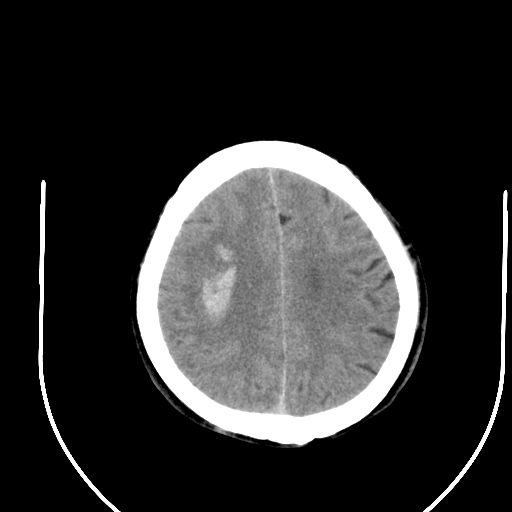

标题: CT24997:M,60Y,突发昏迷30分钟,有高血压病史。 [打印本页]

标题: CT24997:M,60Y,突发昏迷30分钟,有高血压病史。

右侧基底节区脑出血并破溃入脑室。

1右侧基底节脑出血伴脑干出血并破入脑室系统脑疝形成2梗阻性脑积水

1)右侧基底节脑出血伴脑干出血并破入脑室系统。2)大脑镰下疝。3)梗阻性脑积水。

1、右侧基底节脑出血伴脑干出血并破入脑室系统。

2、大脑镰下疝。

3、梗阻性脑积水。